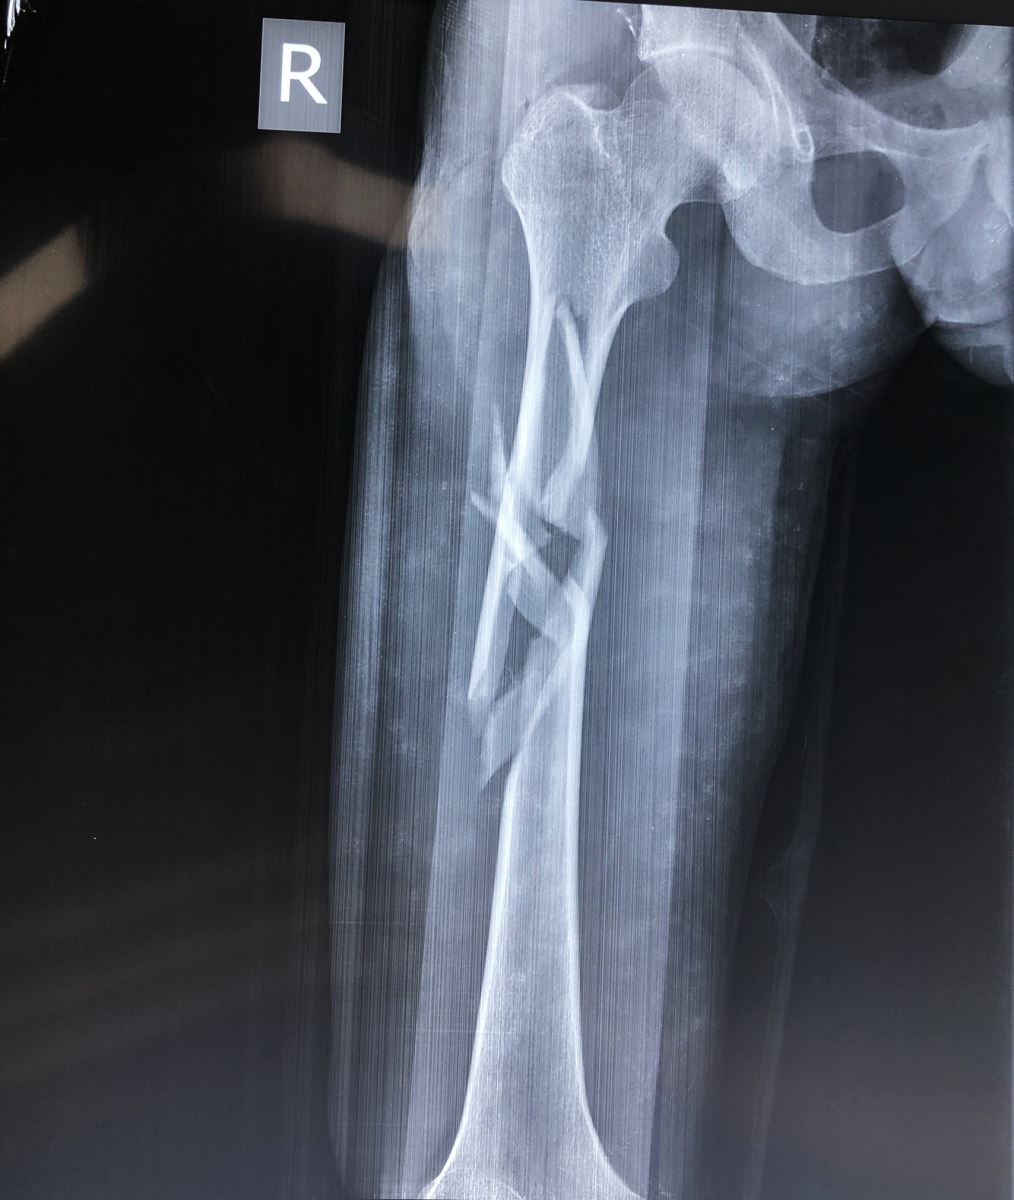

1.2. Đường gãy

Gồm có gãy ngang, gãy chéo, gãy xoắn, gãy 2 ổ hoặc gãy vụn.

- Đường gãy chéo, xoắn: Thường do gập góc kèm theo vặn xoắn cơ thể. Dạng gãy này không vững chắc sau khi nắn

1.3. Sự di lệch

Tuỳ theo vị trí gãy và có các hình thái di lệch khác nhau. Các di lệch thường gặp là gập góc, lệch sang bên, chồng lên nhau, xoay ngoài của đoạn gãy xa.